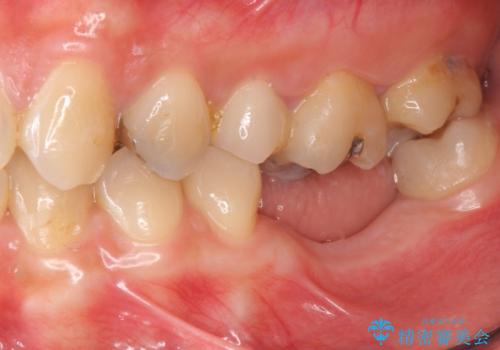

他院で断られた骨造成を伴うインプラント治療

- 虫歯を放置し他院で抜歯後、入れ歯を提案されインプラント治療を希望され来院されました。

CT画像より骨の量は少なくそのままではインプラントの埋入が難しい状態です。